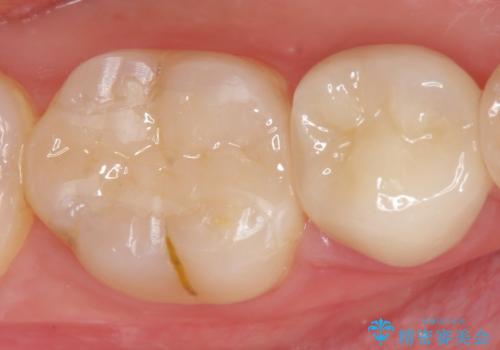

再発した虫歯は神経に近いことが多く、丁寧に除去することで神経を温存し、精密なセラミック修復を行うことで更なる虫歯の再発を防ぎます。

- 19.8万円 (セラミックインレー 仮歯・ジルコニアクラウン)費用は治療当時の料金となります

虫歯の再発を防ぐよう、しっかりと虫歯を除去すること、削り取った部分を封鎖することが重要です。